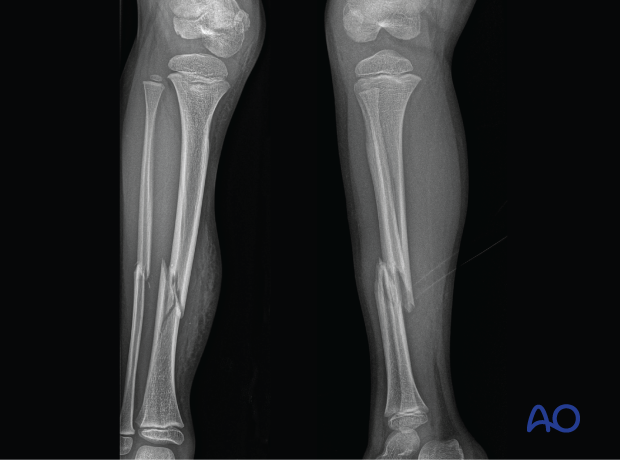

- Simple and multifragmentary fractures of the tibial shaft

This includes detailed procedures on elastic stable intramedullary nailing (ESIN), external fixation, and plate fixation, in addition to nonoperative management with casting and splinting.